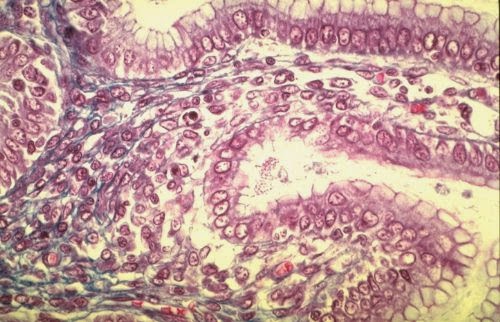

Tissus conjonctifs cours. Tissus conjonctif conjonctifs différents fibres organisme lâche proprement cellules derme

Tissus conjonctif conjonctifs différents fibres organisme lâche proprement cellules derme. Tissus conjonctifs cours